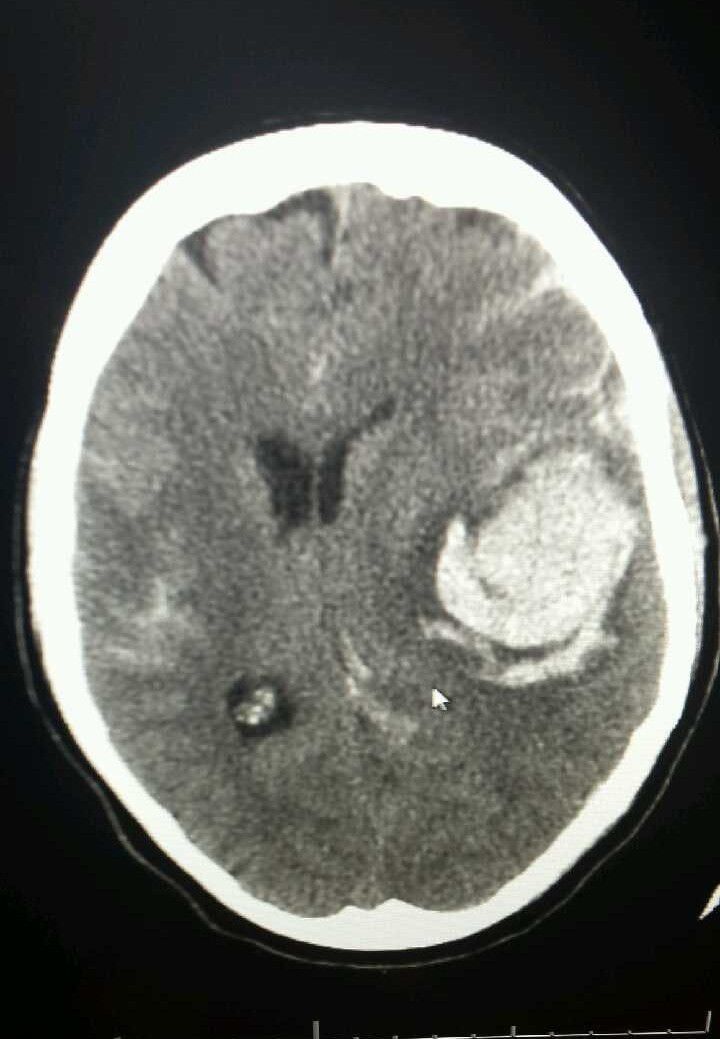

Neurosurgery

Neuro